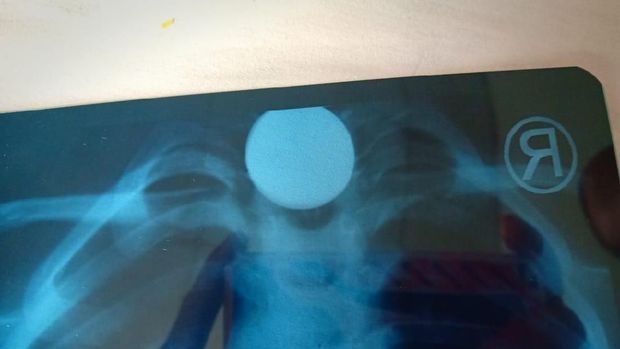

Posisi logam sempat dikhawatirkan menyumbat saluran pencernaan hingga diperkirakan butuh operasi. Foto: Dok. Onlihu |

Posisi logam sempat dikhawatirkan menyumbat saluran pencernaan hingga diperkirakan butuh operasi. Foto: Dok. Onlihu